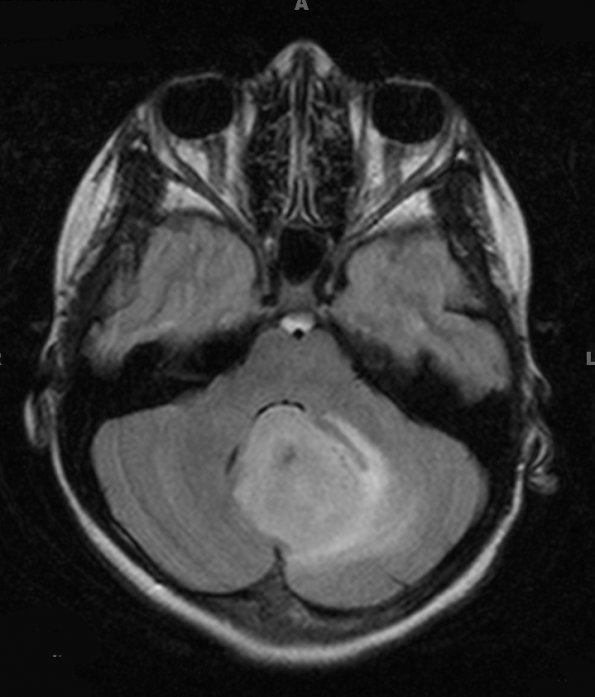

Washington University Experience | NEOPLASMS (GLIAL) | Astrocytoma, pilocytic - Microscopic | 7A1 Astrocytoma, pilocytic (necrosis, Case 7) FLAIR

Case 7 ---- 11 year old female, cerebellum ---- 7A1,2 MRI studies demonstrate the tumor appearance with FLAIR imaging (7A1) and T1-weighted image with contrast (7A2)